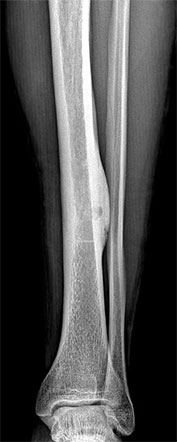

Опухоли костей являются редкими поражениями. Большая часть таких опухолей - доброкачественные образования, которые часто обнаруживаются случайно при радиологических исследованиях, проводимых по другим причинам. Что касается жалоб, они обычно проявляются отеком и болью. В редких случаях они обнаруживаются вследствие вызванного ими перелома в месте их расположения. Наиболее часто встречающимися доброкачественными образованиями являются остеоид-остеома, остеохондрома (экзостоз), энхондрома, неоссифицирующая фиброма, эозинофильная гранулема, простая костная киста, фиброзная дисплазия и внутрикостная липома / ганглия.